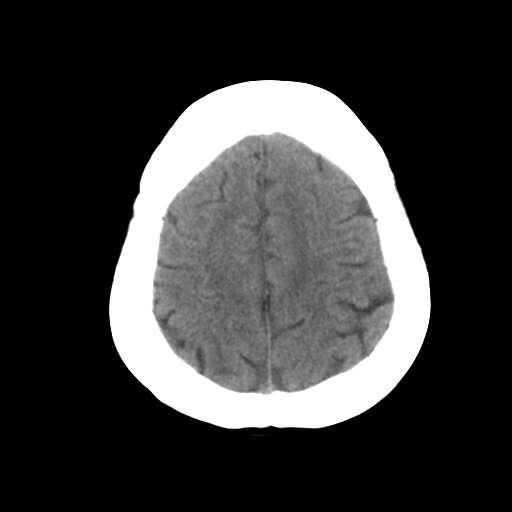

一台GE CT机突然出现下图伪影,请问是何原因?

并不是一直都有此伪影

这是设备原因造成的伪影一种伪影,

需要重新校准,

若不能矫正的话,那就没什么好办法了,

除非换配件

是不是原配球管啊,我院有台机器外圈有伪影是球管原因.

这种伪影一般还有个特点

在做薄层扫面时容易出现,一般是小于5mm,

但是在做常规10mm扫面时不会出现

这种现象并非一直出现,不分时间段,球管是租赁的,可能与电源有关

你有做一套的模和空气校正吗?没做好也会出这种情况的,一样是会有时好时坏的故障出的。